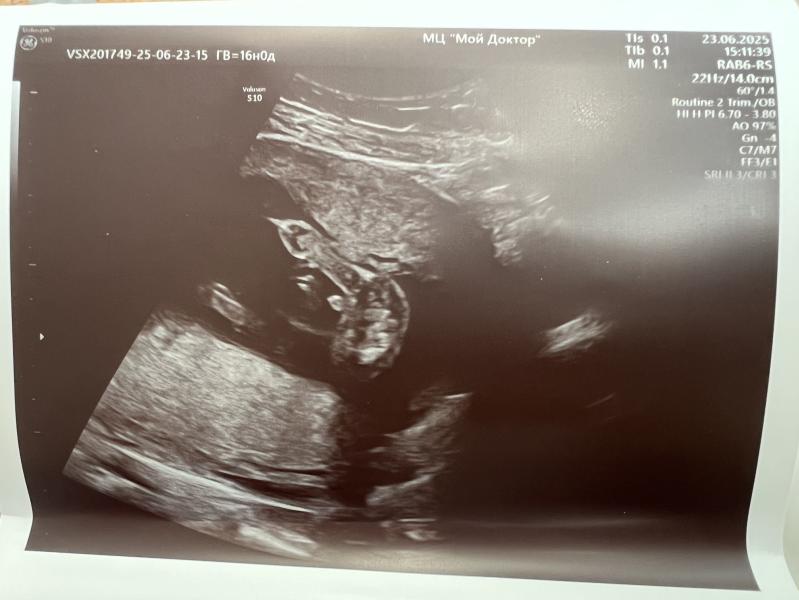

Сегодня ровно 16 недель, сходила на узи. Тут, думаю, понятно кто у нас будет))

Прям свечка торчит ))) поздравляю !)))

👏 Поздравляю с сыночком)